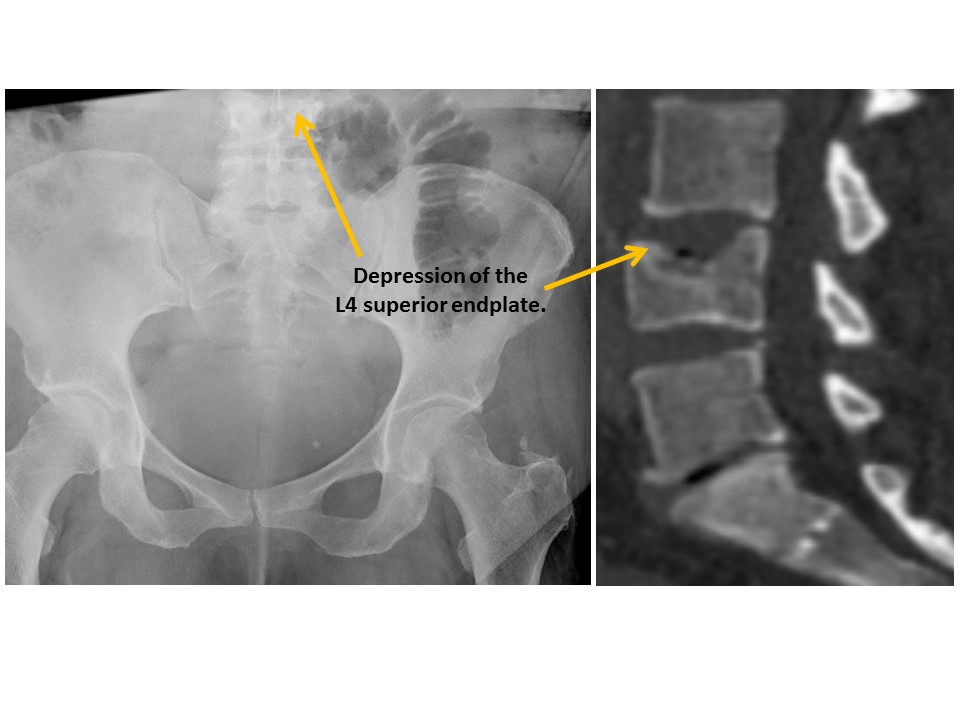

VISUALIZED LUMBAR SPINE

There are compression fractures. [Yes/No]